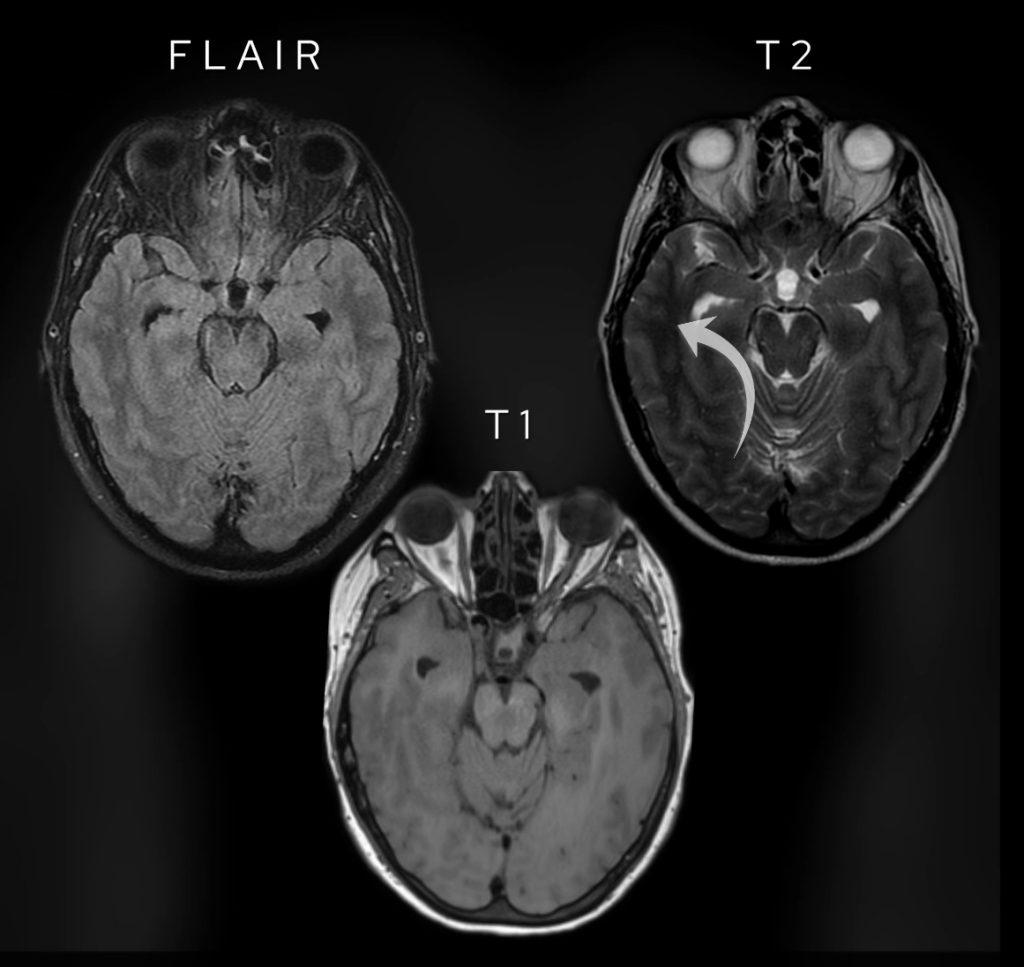

One of the key sequences used in brain imaging is FLAIR (Fluid Attenuated Inversion Recovery). It’s a variation of T2-weighted imaging but with fluid (like CSF) suppressed, making it excellent for detecting inflammation and oedema. Have a look at the images below and compare the fluid within the CSF, the grey matter and the white matter.

Note the difference between FLAIR images and T1 weighted and T2 weighted images. Fluid is dark like on T1 weighted images. Note the white matter (arrowed on the T2 image) is brighter than grey matter only on T1 weighted images.

Like on T2-weighted images, oedema shows as bright but unlike T2-weighted images fluid is dark (as can be seen on T1-weighted images). Have a look at the table below which highlights some of the key differences.

- FLAIR: The lesion is bright, indicating abnormal tissue.

- T2-weighted: It’s not as bright as CSF but slightly hyperintense compared to grey and white matter.

- T1-weighted: It appears brighter than the surrounding brain tissue.

- Post-contrast images: There is no significant enhancement, ruling out highly vascular lesions.

FLAIR images show hyperintensity within the lesion whilst T2-weighted images show the lesion is hypointense to CSF.

T1 pre and post contrast sagittal images show no appreciable enhancement in the lesion post intravenous gadolinium contrast.